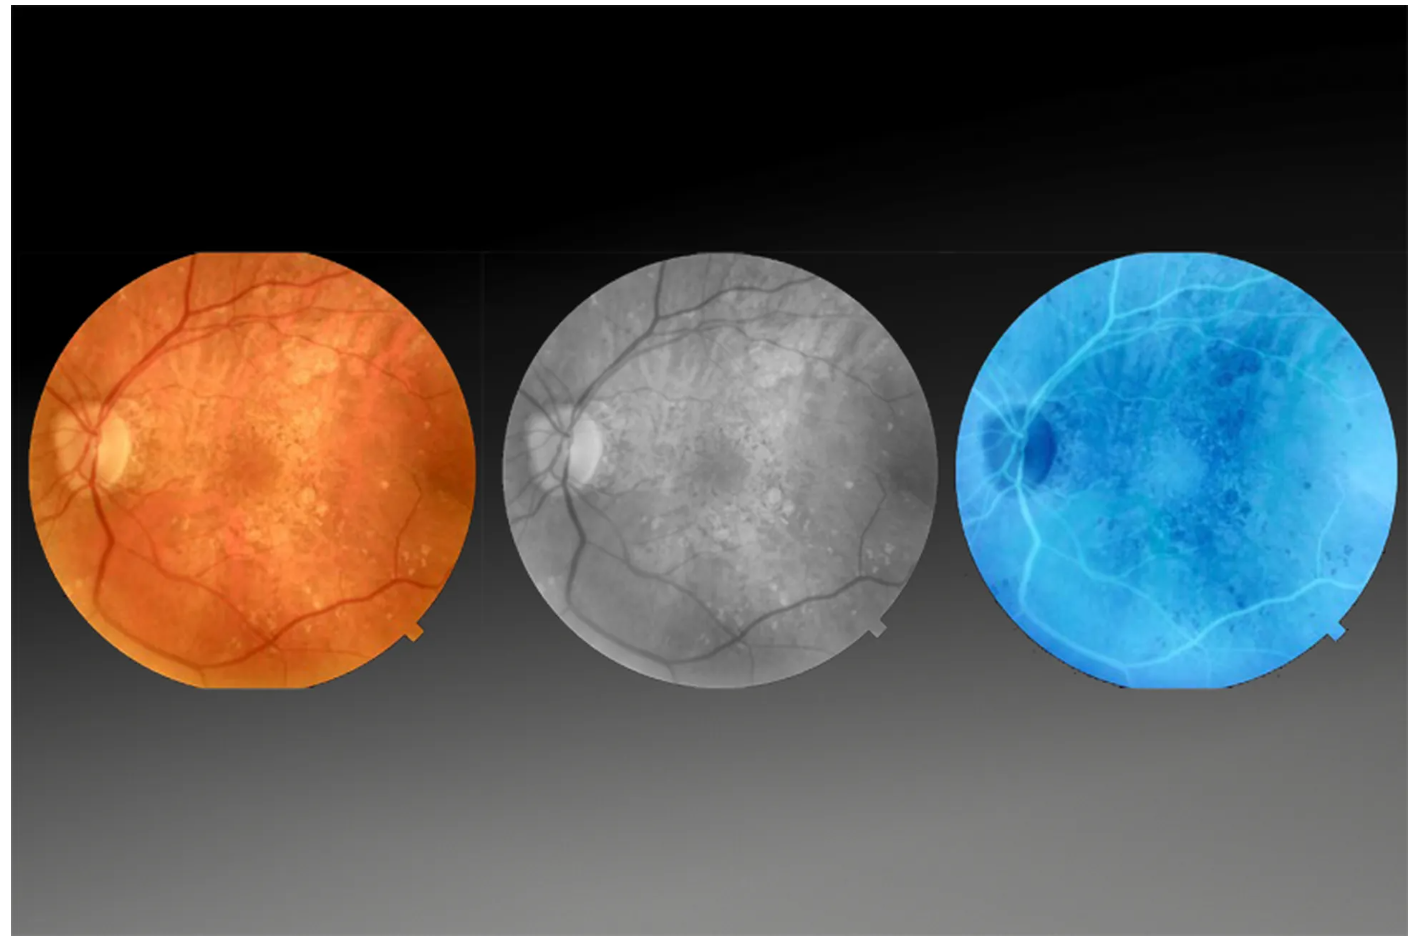

Оптический когерентный томограф Optovue Solix обладает повышенной скоростью сканирования — 120 000 А-сканов в секунду. SOLIX предоставляет множество инструментов для нового поколения борьбы с заболеваниями, которые повышают пропускную способность и обеспечивают превосходный уход за пациентами. В отличие от томографов более ранних поколений ОКТ SOLIX OPTOVUЕ может определять наличие конкрементов и новообразований сосудов сетчатки и хориоидеи, позволяет получать максимально точную послойную визуализацию структур глаза.

- Встроенная фундус-камера;

- Программа AngioAnaliticsTM для количественного анализа сосудов сетчатки;